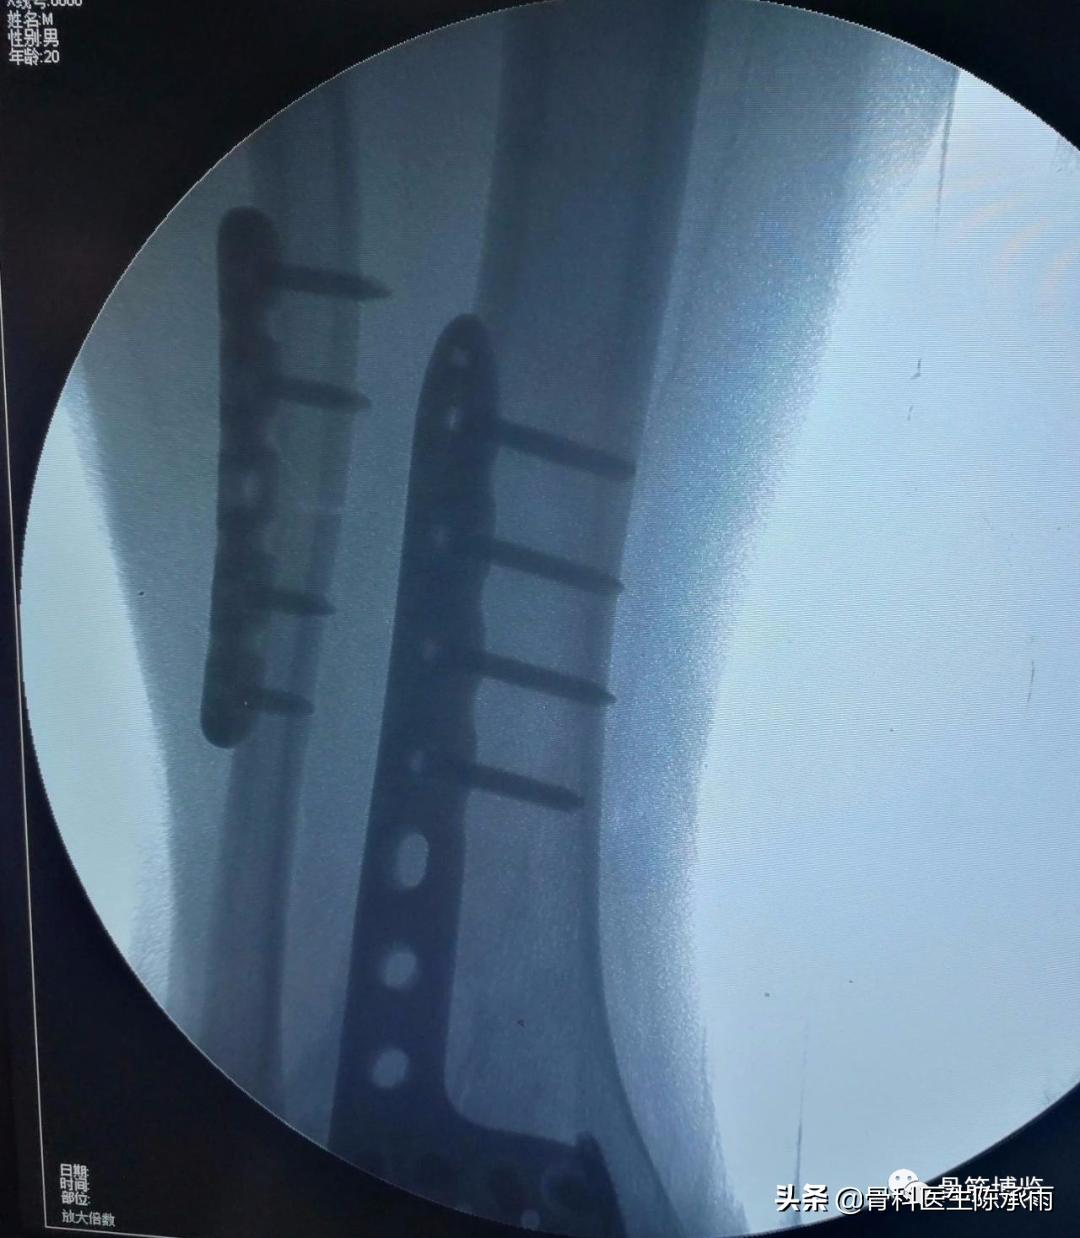

6、前踝解剖板尽量靠近关节面,以起支撑固定作用。

7、内踝骨折可于前侧切口内显露复位,经皮小切口固定。

8、腓骨骨折及后踝可于同一切口内进行。

骨折固定满意。